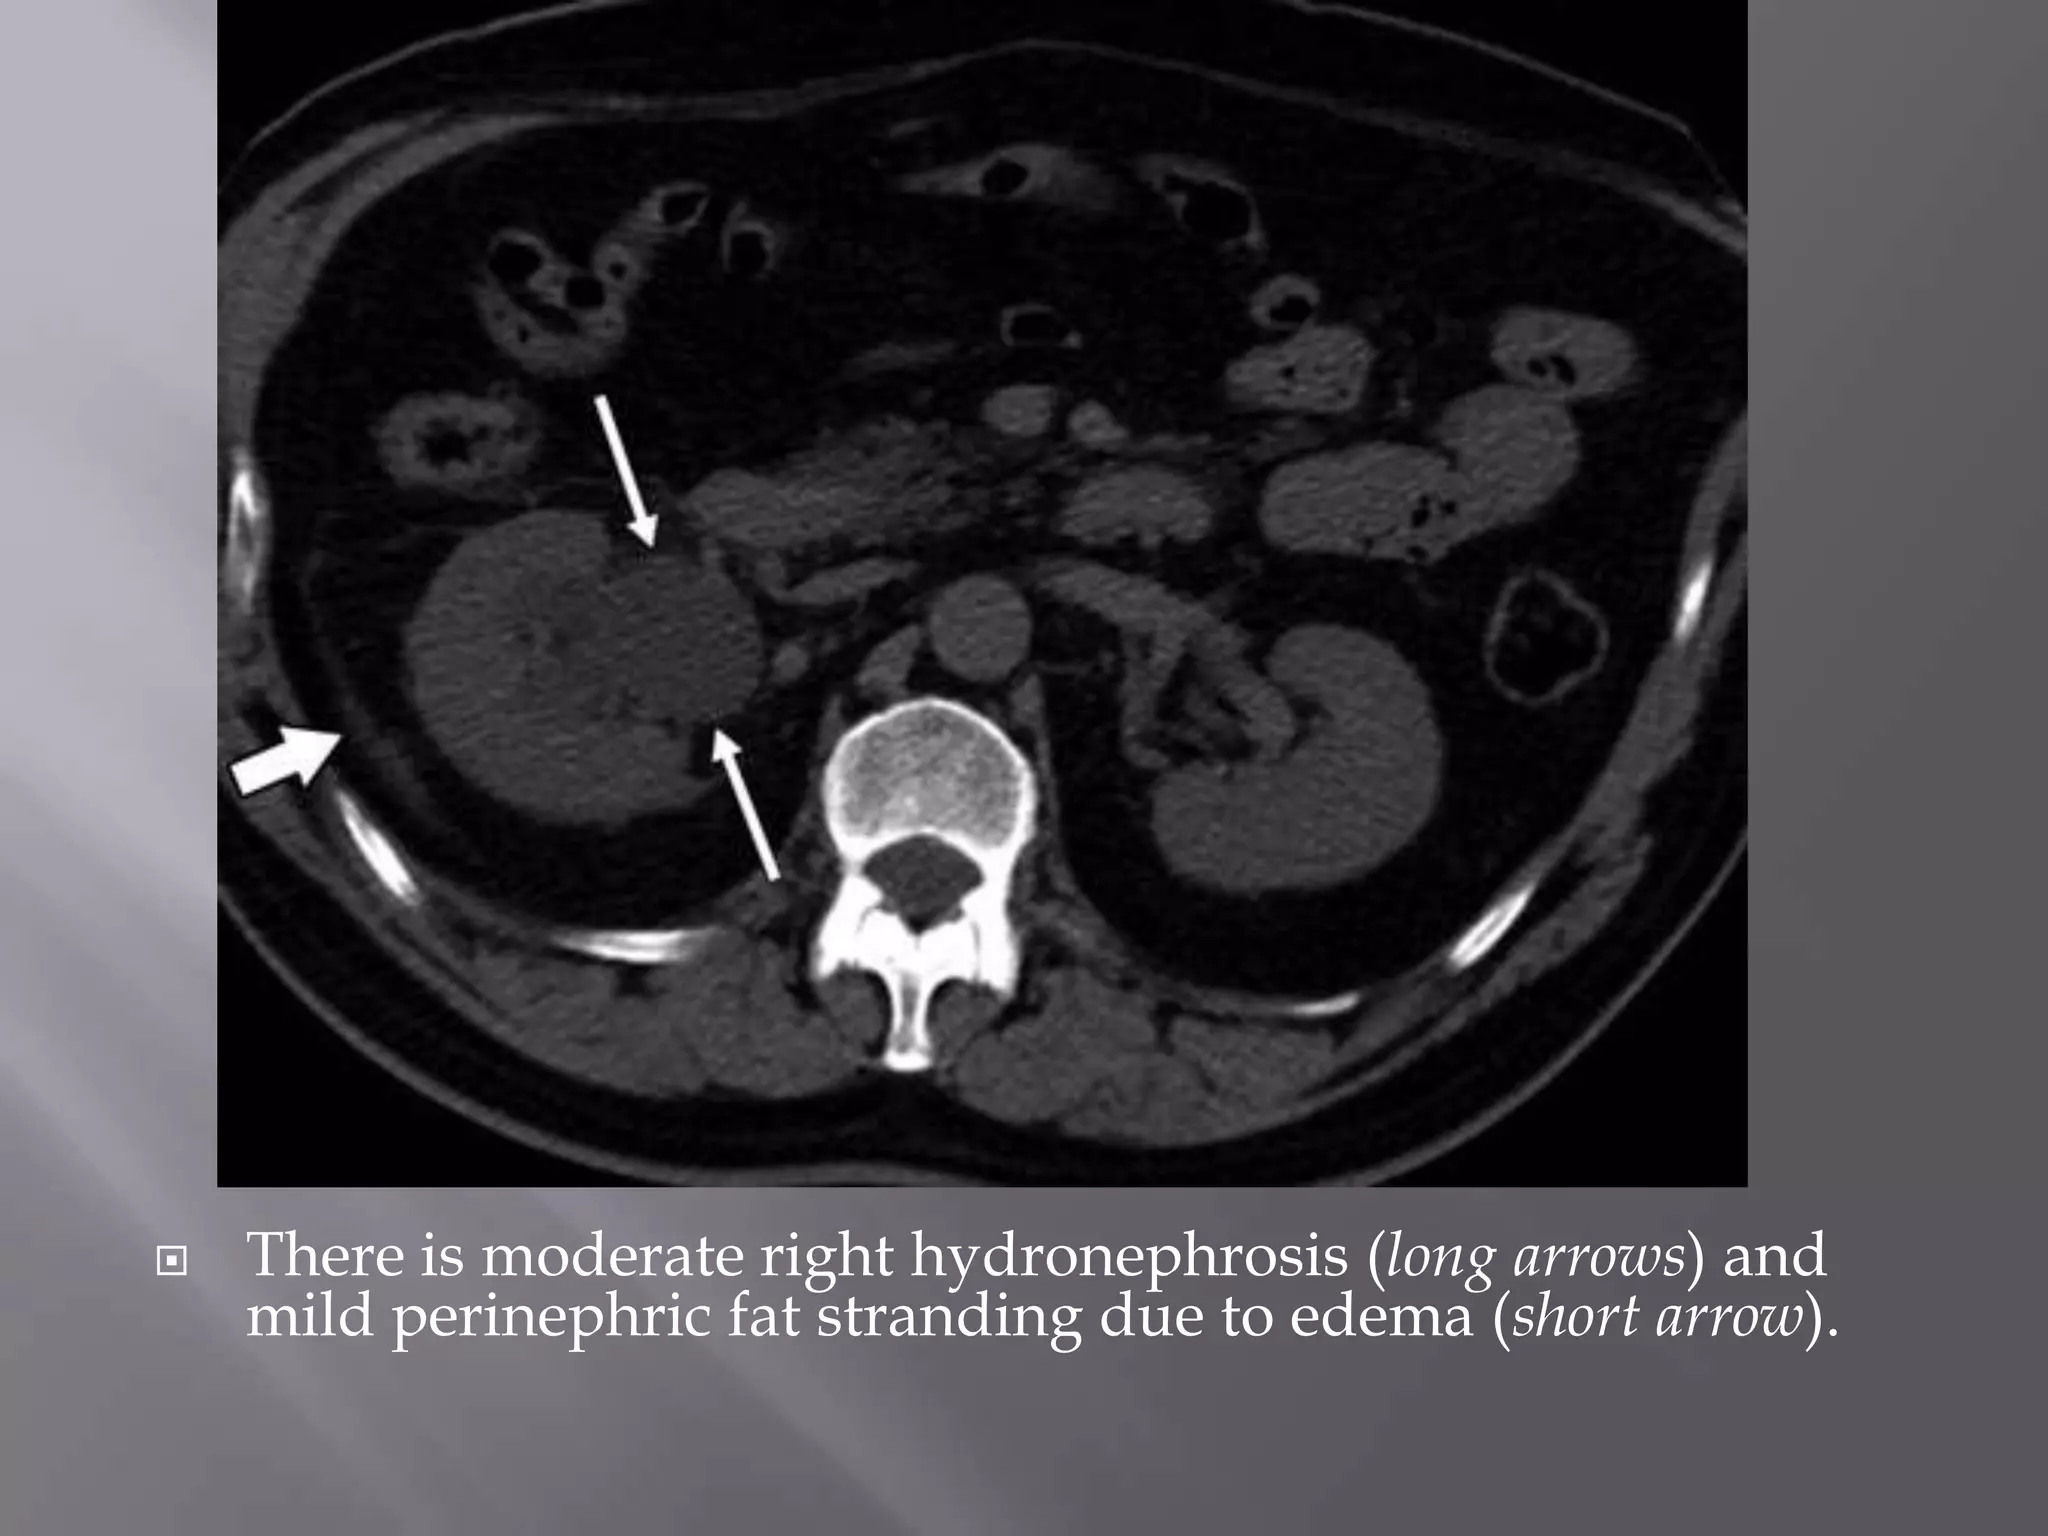

 There is moderate right hydronephrosis (long arrows) and

mild perinephric fat stranding due to edema (short arrow).

 There ismoderate right hydronephrosis (long arrows) and mild perinephric fat stranding due to edema (short arrow).